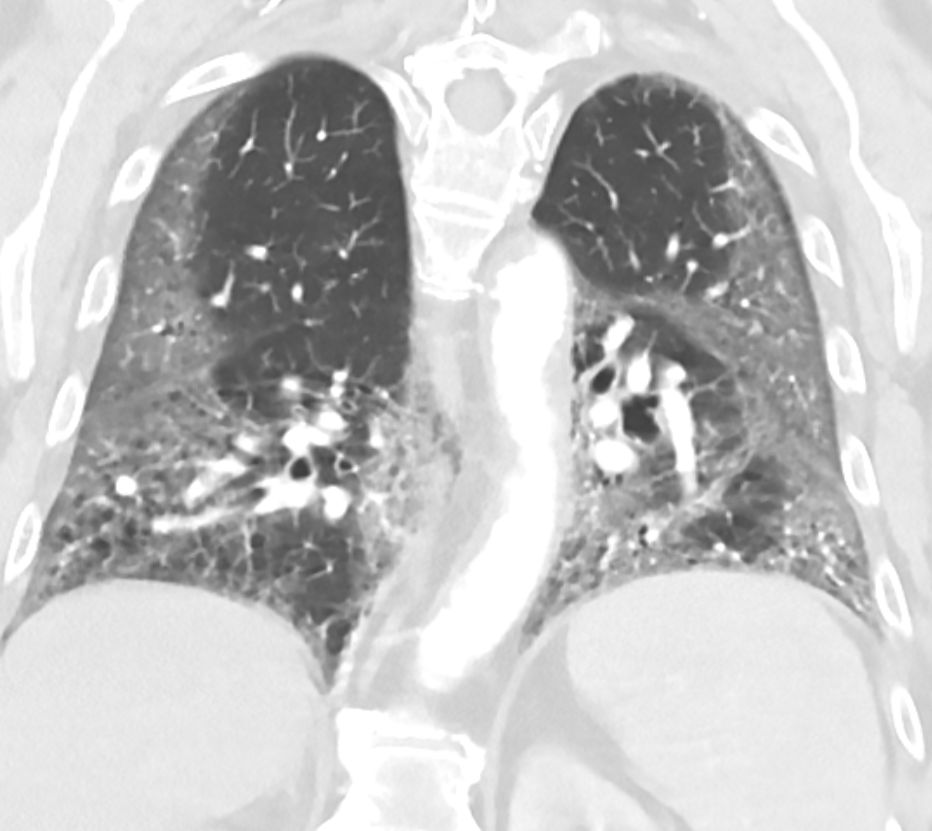

Another form of lung disease is referred to as restriction, or difficulty expanding the lungs. Restriction decreases the volume of the lungs and, subsequently, the amount of air they can take in. Restriction often results from the formation of scar tissue, also called fibrosis, in the lungs due to injury.

Fibrosis thickens the walls of the alveoli, which makes gas exchange with the blood more difficult. This type of scarring can occur in chronic lung diseases, such as idiopathic pulmonary fibrosis, or as a result of severe lung damage in a condition called acute respiratory distress syndrome, or ARDS.

Researchers have also found that patients who have recovered from COVID-19, especially those who had severe disease, can later develop restrictive lung disease. COVID-19 patients who require a ventilator may also have recovery rates similar to those who require a ventilator for other conditions. Long-term recovery of lung function in these patients is still unknown. Drugs treating fibrotic lung disease after COVID-19 are currently undergoing clinical trials.